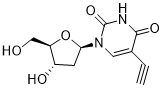

馬鞍山致研生物醫(yī)藥科技有限公司成立于馬鞍山市鄭浦港新區(qū)現(xiàn)代產(chǎn)業(yè)園。公司專(zhuān)注于生物小分子、醫(yī)藥中間體相關(guān)產(chǎn)品的研發(fā)和生產(chǎn),產(chǎn)品主要包括DNA亞磷酰胺單體、RNA亞磷酰胺單體、特殊單體以及按照客戶(hù)要求定制的RNA和DNA,并且公司提供定制合成等方面的研究服...

馬鞍山致研生物醫(yī)藥科技有限公司成立于馬鞍山市鄭浦港新區(qū)現(xiàn)代產(chǎn)業(yè)園。公司專(zhuān)注于生物小分子、醫(yī)藥中間體相關(guān)產(chǎn)品的研發(fā)和生產(chǎn),產(chǎn)品主要包括DNA亞磷酰胺單體、RNA亞磷酰胺單體、特殊單體以及按照客戶(hù)要求定制的RNA和DNA,并且公司提供定制合成等方面的研究服...